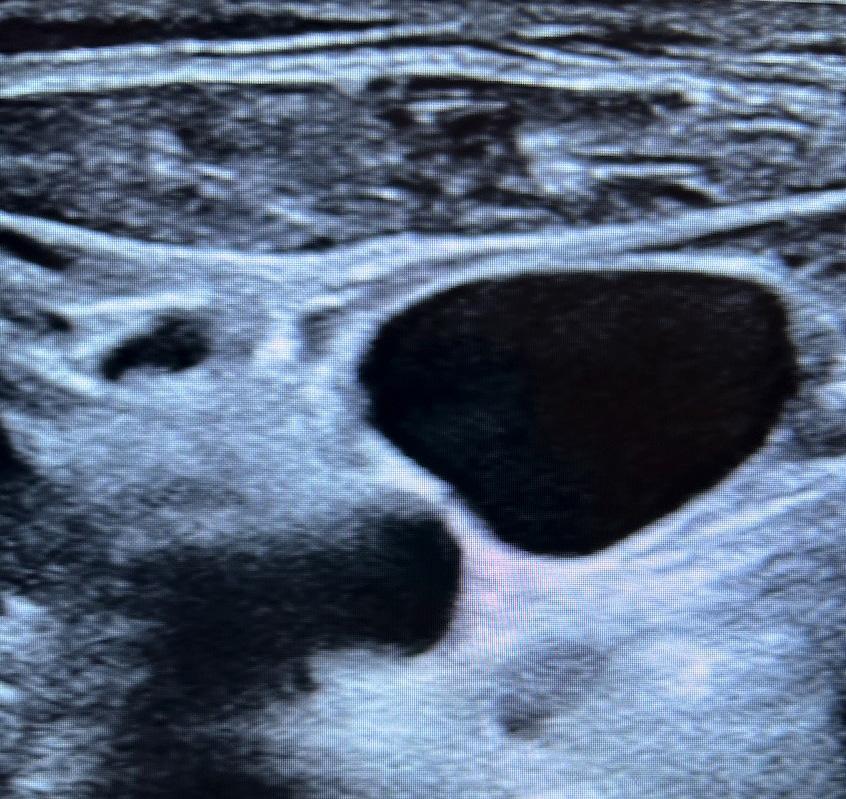

In the case covered in this article, an 85-year-old man with septic shock caused by a perforated sigmoid colon was profoundly hypovolemic and required crystalloid resuscitation and dual vasopressors. Ultrasound revealed that his internal jugular vessels were completely collapsible. Initial attempts to place the catheter were unsuccessful due to vessel collapse. The Trendelenburg position did not adequately dilate the internal jugular vein, as shown in Image 1. However, using a passive leg raise, significant dilation of the internal jugular vein was observed, enabling successful cannulation (Image 2).